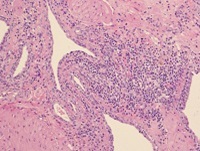

Cytologie of histologie

Cytologisch beeld van BPH van een zuigbiopt (links) en een percutaan biopt